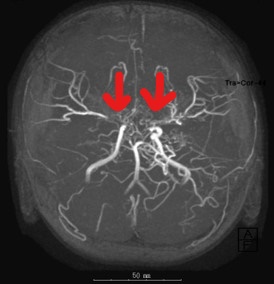

① MRI 및 MRA(자기공명혈관조영술)

- 뇌혈관의 좁아진 부위 및 대체 혈관망(모야모야 혈관)을 시각화함

- 뇌조직의 손상, 허혈 또는 출혈 여부도 동시에 확인 가능

- 모야모야 혈관의 특성적인 모습(연기처럼 퍼짐)을 확인할 수 있음